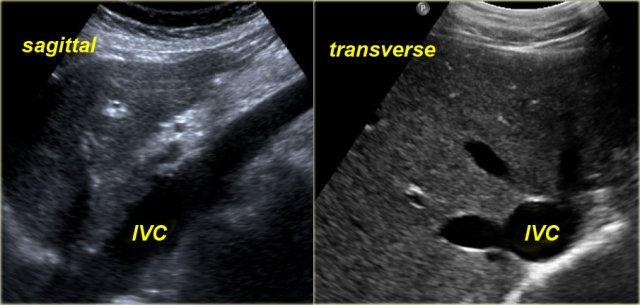

Dilatation of IVC and hepatic veins on US images in a patient with RV failure Dilatation of IVC and hepatic veins on US images in a patient with RV failure

Sonographic signs of RV failure:

• Dilatation of the inferior vena cava (IVC) and hepatic veins

• Hepatomegaly

• Ascites

The indication for ultrasound examination in many of these patients is abnormal liver function tests.

It is therefore important to consider the possibility of RV failure when a patient presents with liver enzyme abnormalities.

Under normal conditions dynamic ultrasound will demonstrate changes in caliber of the IVC.

These changes in caliber can be attributed to variations in blood flow in the IVC in accordance with the respiratory and cardiac cycles.